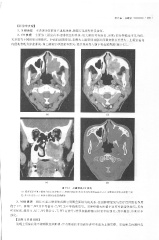

Page 361 - 医学影像诊断学